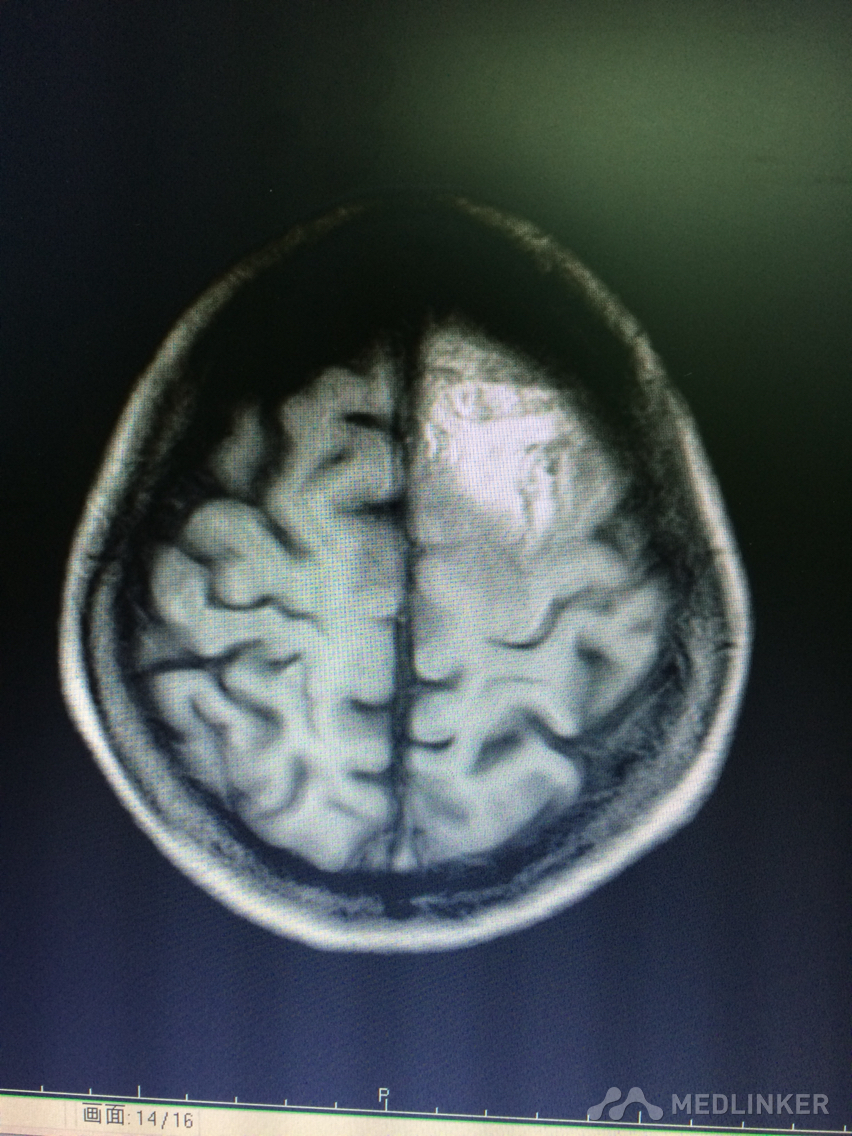

看看这MRI,奇怪啊,快来帮忙看看?

患者78岁老年女性,以精神行为异常和认知障碍为主要表现